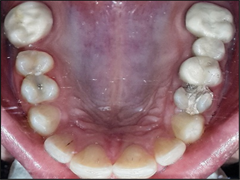

The present study was carried out in the department of periodontics and community dental sciences (PCS), college of dentistry, king Khalid university, Saudi Arabia for a period of 6 months from January 2016 to June 2017. A total of 292 patients (152 males) and (140 females) were evaluated for the effect of the dental restorations type of marginal bone loss among some patients being treated for chronic periodontitis. They were divided according to dental reconstructions into three groups, group I included 102 patients (52 males and 50 females) without dental reconstructions (control group), group II included 95 patients (50 males and 45 females) patients received amalgam class II fillings and group III included 95 patients (50 males and 45 females) received fixed bridge denture (FPDs) (Figure 1 and Figure 2).

Figure 1. Clinical examination of patient with amalgam filling.